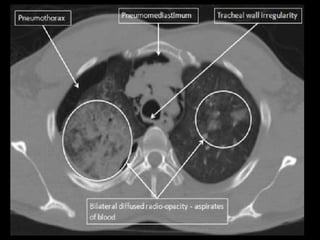

Chest CT scan :-

• Intrapleural gas along with loculated pneumothoraces.

• Pleural effusion, pneumothorax.

RADIOLOGICAL FINDINGS Chest X-ray:- • Hyper translucency between the lung & thoracic cage. • Razor sharp border of the collapsed lung. • Shifting of mediastinum on the opposite side of injury. Chest CT scan :- • Intrapleural gas along with loculated pneumothoraces. • Pleural effusion, pneumothorax. Chest Ultrasound :- • Smooth horizontal echogenic lines are seen above and below the pleural lines. • Absence of lung sliding and B - lines.